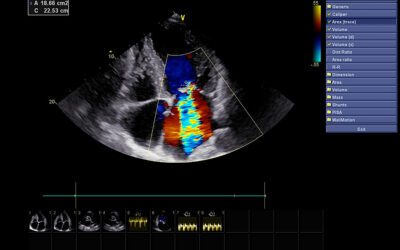

Important Facts About Echocardiograms

An echocardiogram is an ultrasound of the heart. It uses sound waves to produce the images.The imaging enables your healthcare provider to examine...